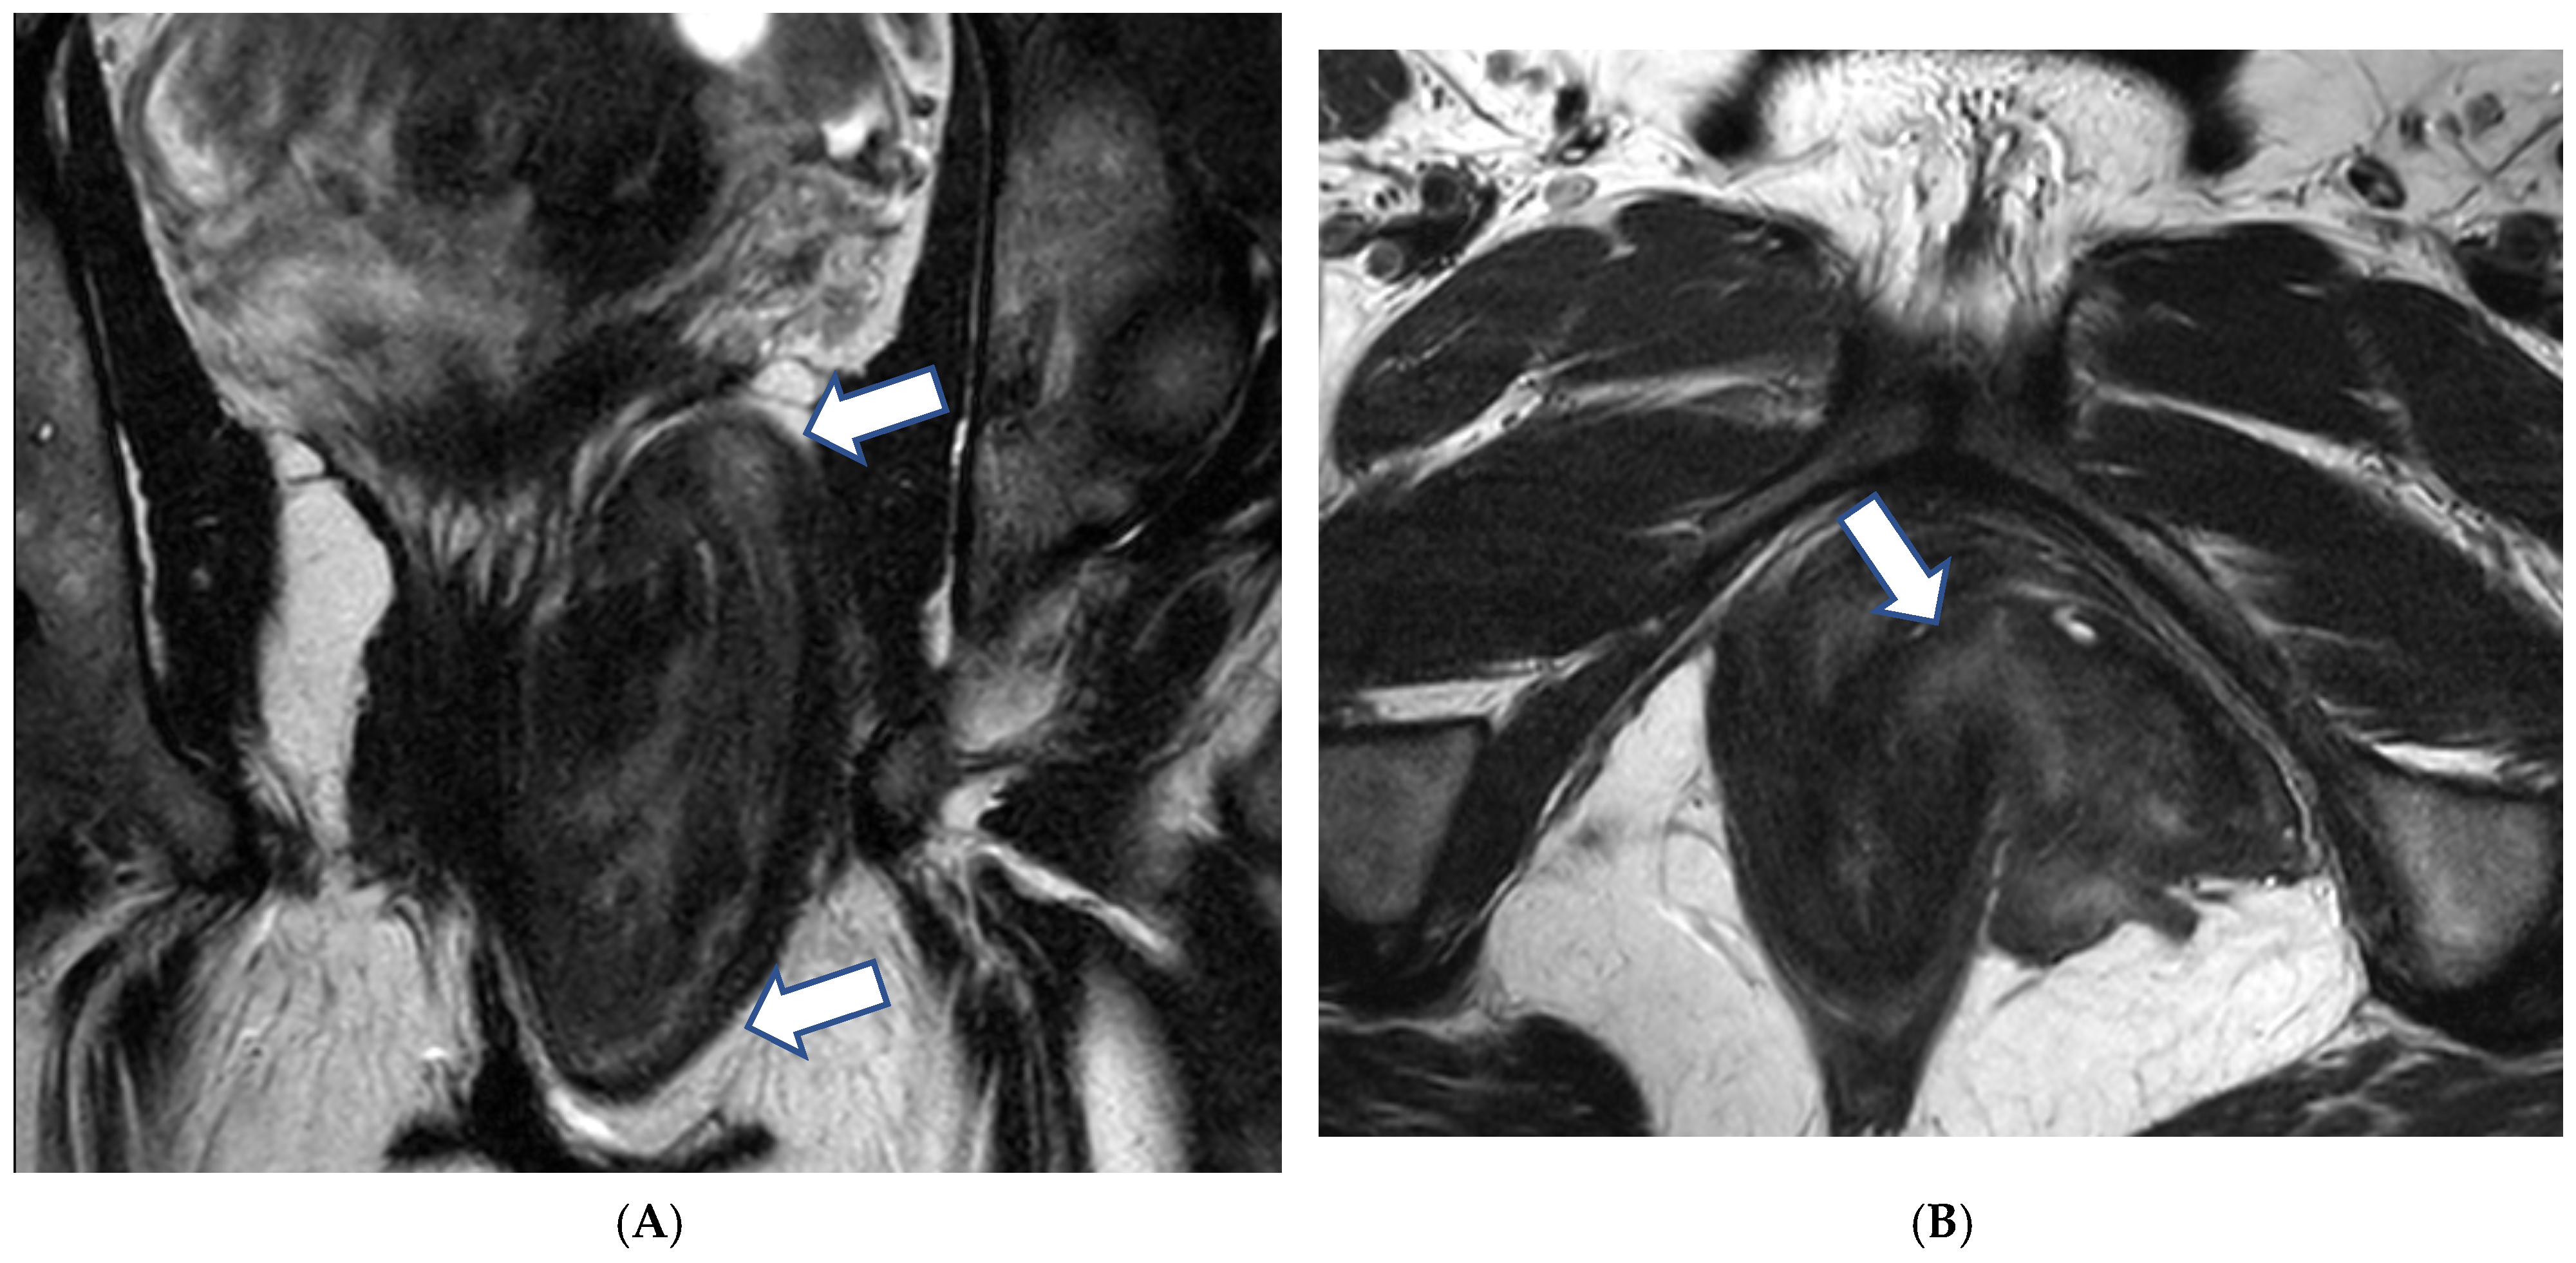

3.1.2. Imaging

3.3.2. Imaging